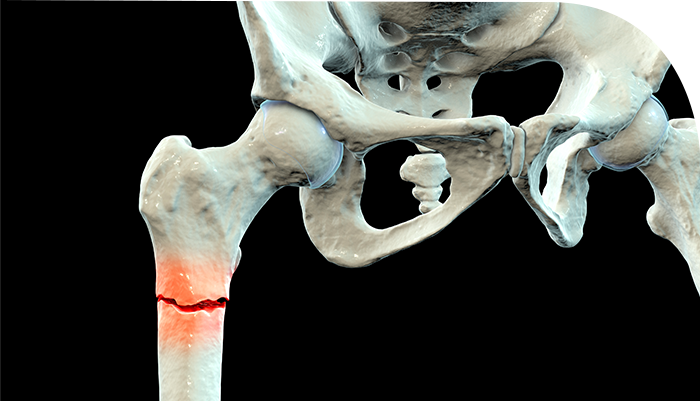

°ñÀýÀ̶õ ¿ÜºÎÀÇ Ãæ°Ý¿¡ ÀÇÇØ »À°¡ ºÎ·¯Áö´Â °ÍÀÔ´Ï´Ù. »À, °ñ´ÜÆÇ, °üÀý¸éÀÇ ¿¬¼Ó¼ºÀÌ ¿ÏÀü ȤÀº ºÒ¿ÏÀüÇÏ°Ô ²÷¾îÁø »óÅÂÀÔ´Ï´Ù.

°ñÆí¼ö¿¡ µû¶ó ºÐ¼â°ñÀýÀÌ µÉ¼öµµ ÀÖ°í, ºÐÀý¼º °ñÀýÀÌ µÉ ¼öµµ ÀÖ½À´Ï´Ù. °ñÀý¸é ¹æÇâ¿¡ µû¶ó ´Ù¾çÇÑ °ñÀý ÇüŰ¡ ¹ß»ýÇÒ ¼ö ÀÖ½À´Ï´Ù.

»óÁö ȤÀº ÇÏÁöÀÇ ½Å°æ ¹× Ç÷°üÀÇ ¼Õ»óÀÌ µ¿¹ÝµÉ ¼ö ÀÖ¾î, Á¶±â¿¡ Áø´ÜÇÏ°í ºü¸¥ °ñÀý Ä¡·á°¡ ÇÊ¿äÇÕ´Ï´Ù.